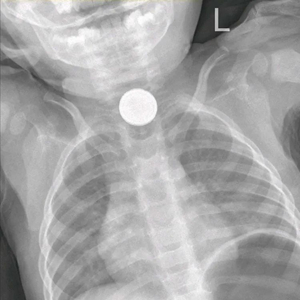

当晚接诊的是宁夏医科大学总医院儿童急诊,做了胸片检查,提示异物位于食道上段,于是请耳鼻喉头颈外科会诊,在局麻下做了食道镜检查,但电池的个头比加大,直径2厘米左右,接近5分钱硬币,而且孩子吞下去的是2枚电池,取出非常困难,甚至滑落到了更深的地方。

医院再次复查正位腹平片,发现电池掉进了胃内,遂转诊到小儿外科。考虑到胃酸腐蚀电池后会引起电池内部化学物质泄露,引起中毒及消化道损伤,小儿外科立即收住院,同时联系消化内科及麻醉科,准备做手术,通过胃镜探查并取出电池。